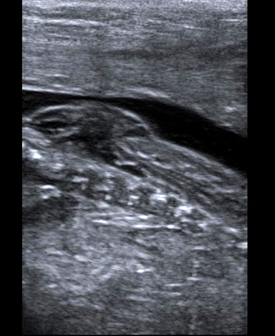

Myelomeningocele high resolution ultrasound.

- Fetal brain and spine anomalies including Spina Bifida, Fetal Ventriculomegaly, Dandy-Walker Malformation, and Agenesis of the Corpus Callosum.

Further attesting to our expertise in fetal imaging, UCSF is one of the three centers that performed the prenatal imaging for a recently published New England Journal of Medicine article on prenatal surgery for myelomeningocele.